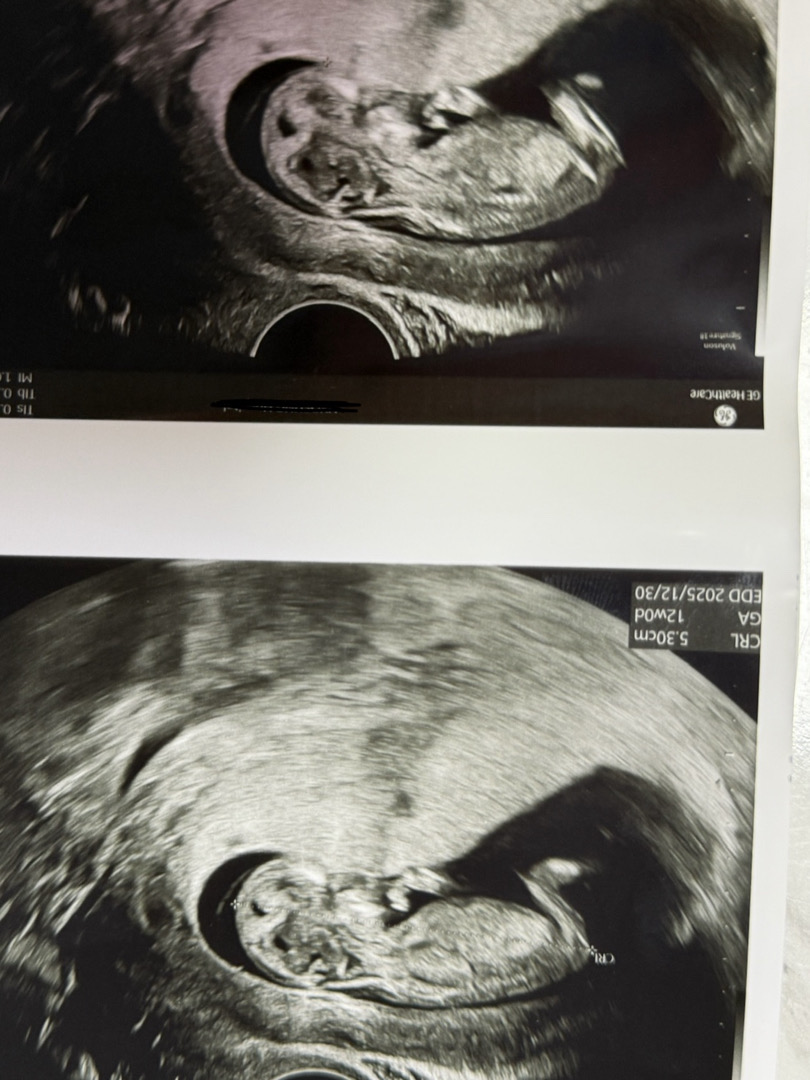

오늘 초음파 보고왔는데 각도법으로 성별 알수있을까요~? 살짝 애매한거같기도해서요ㅠㅠㅠㅠ 한번 봐주세요~